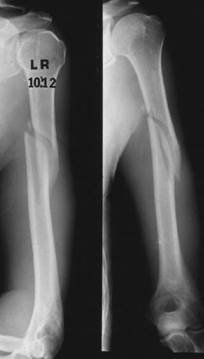

A 35-year-old left-handed man sustained this injury whilst arm wrestling.

Describe these radiographs to me. How would you go about managing this injury?

T hese radiographs show an oblique mid-shaft fracture of the left humerus. My initial management would be to give the patient analgesia and a collar and cuff sling. I would take a mechanism of injury history and then examine the arm assessing the soft tissues (?open/?compartment syndrome) and distal neurovascular status (particularly radial pulse and radial nerve function). I would then take a more detailed general history โ€” personality of patient.

Y ou could treat this non-operatively with analgesia gravity traction in collar and cuff ; however, I would have a low threshold for fi xation in distal third fractures that are prone to slip into varus.

For operative fi xation I would use a posterior approach: z Position: patient on their side and the arm over a well-padded roll z Approach: using a midline skin incision the plane is between the lateral and long head triceps โ€” w hich is easier to find proximally (no true internervous plane, but muscles are innervated very high up so are not denervated). Look for the radial nerve and profunda A in the spiral groove coming medial to lateral โ€” find/protect. I would then split the medial head in the line of fibres on to the bone (subperiosteal) more distally; beware the ulna nerve as it comes from the anterior compartment to the posterior compartment distally on the medial side

zReduction and fixation: I would use a lag screw (large fragment set) and then a 4.5-mm broad DCP with four bicortical screws on each side (screws are offset)

zClosure: I would document the position of the nerve in relation to the plate

It is documented by the casualty offi cer that the patient has dense radial nerve palsy. How would this alter your management?

Treat radial nerve injury expectantly (90 % are neuropraxias and recover within 3โ€“4 months). Provide a wrist splint (in extension) for wrist drop/physio to maintain passive range of movement.

Youโ€™ve managed his radial nerve palsy expectantly, but after 4 months there has been no improvement. What would you do now?

I would organize nerve conduction and electromyography (EMG) studies. If these showed a neuropraxia, I would continue to monitor expectantly. If the muscle is denervated (axon or neurotemesis) muscle will show fi brillation potentials on EMGs (secondary to a hypersensitive post-synaptic membrane and random release of pockets of acetylcholine). I would refer to the local peripheral nerve injury specialist unit (wait at least 6 months).

What are the principles of tendon transfers? Which would you use here?

Tendon transfer is a late option, the principles of which are:

z A supple joint with full range of passive motion z A healthy donor which is expendable, with grade 5 Medical Research Council (MRC) power (lose one grade with transfer), has adequate excursion, and is a synergist with a straight line of pull

z Good recipient site โ€” tendon of paralysed muscle (if this is the reason for transfer)

z For a high radial nerve palsy common transfers include pronator teres to extensor carpi radialis brevis (ECRB_, palmaris longus to extensor pollicis longus (EPL) and flexor carpi radialis (FCR) to extensor digitorum (ED)